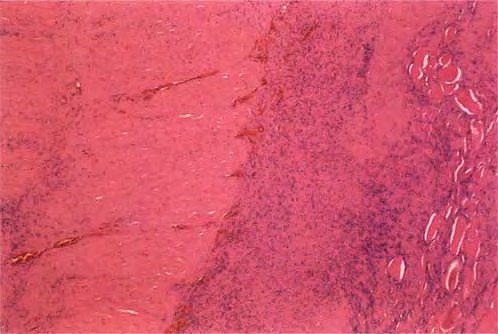

Necrotising fasciitis = التهاب اللفافة النخري